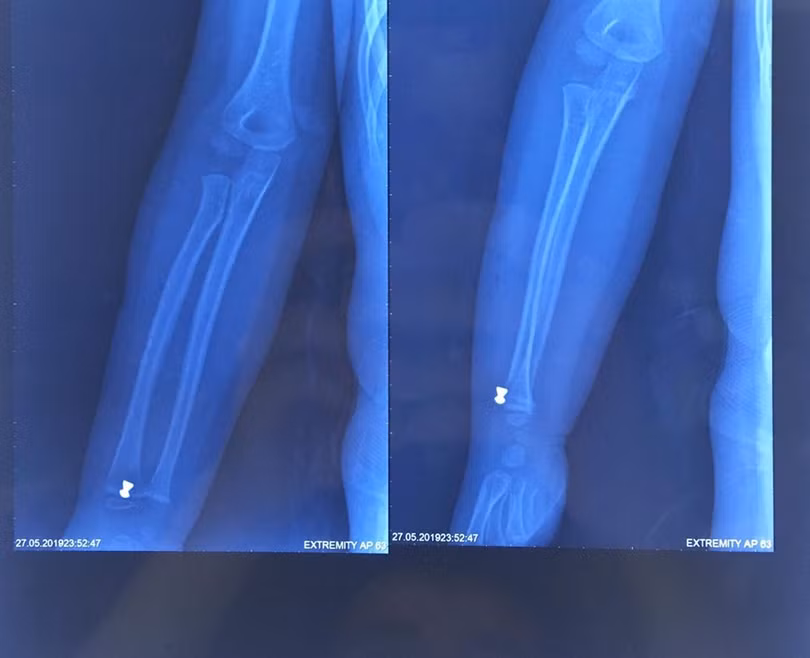

Trước đó, ngày 27/5, bé N.H.K, 5 tuổi ở Sóc Sơn, Hà Nội, được chuyển đến cấp cứu tại Bệnh viện Xanh Pôn trong tình trạng cẳng tay phải bị thương do hỏa khí. Gia đình bé cho biết, trong khi chơi trốn tìm cùng bạn, bé vô tình bị trúng đạn súng hơi do người dân bắn chuột. Gia đình đã đưa bé đến cấp cứu tại Bệnh viện Đa Khoa Sóc Sơn và sau đó là Bệnh viện Xanh Pôn. Tại đây, các bác sĩ đã khám và làm các chỉ định cận lâm sàng cho bé. Kết quả chụp XQ cho thấy, cẳng tay phải của cháu bị găm dị vật 0.5 cm, nên ngay lập tức, bé được chỉ định mổ cấp cứu để lấy dị vật.